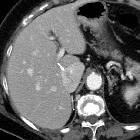

Isolated

intracaval recurrence of resected renal carcinoma. Follow-up contrast-enhanced CT after sunitinib therapy showed dramatic size decrease of tumor thrombosis (a, b) at six months (arrows) and only a small filling defect (c, d) at three years (arrows).

intracaval recurrence of resected renal carcinoma. Follow-up contrast-enhanced CT after sunitinib therapy showed dramatic size decrease of tumor thrombosis (a,b ) at six months (arrows) and only a small filling defect (c, d) at three years (arrows).